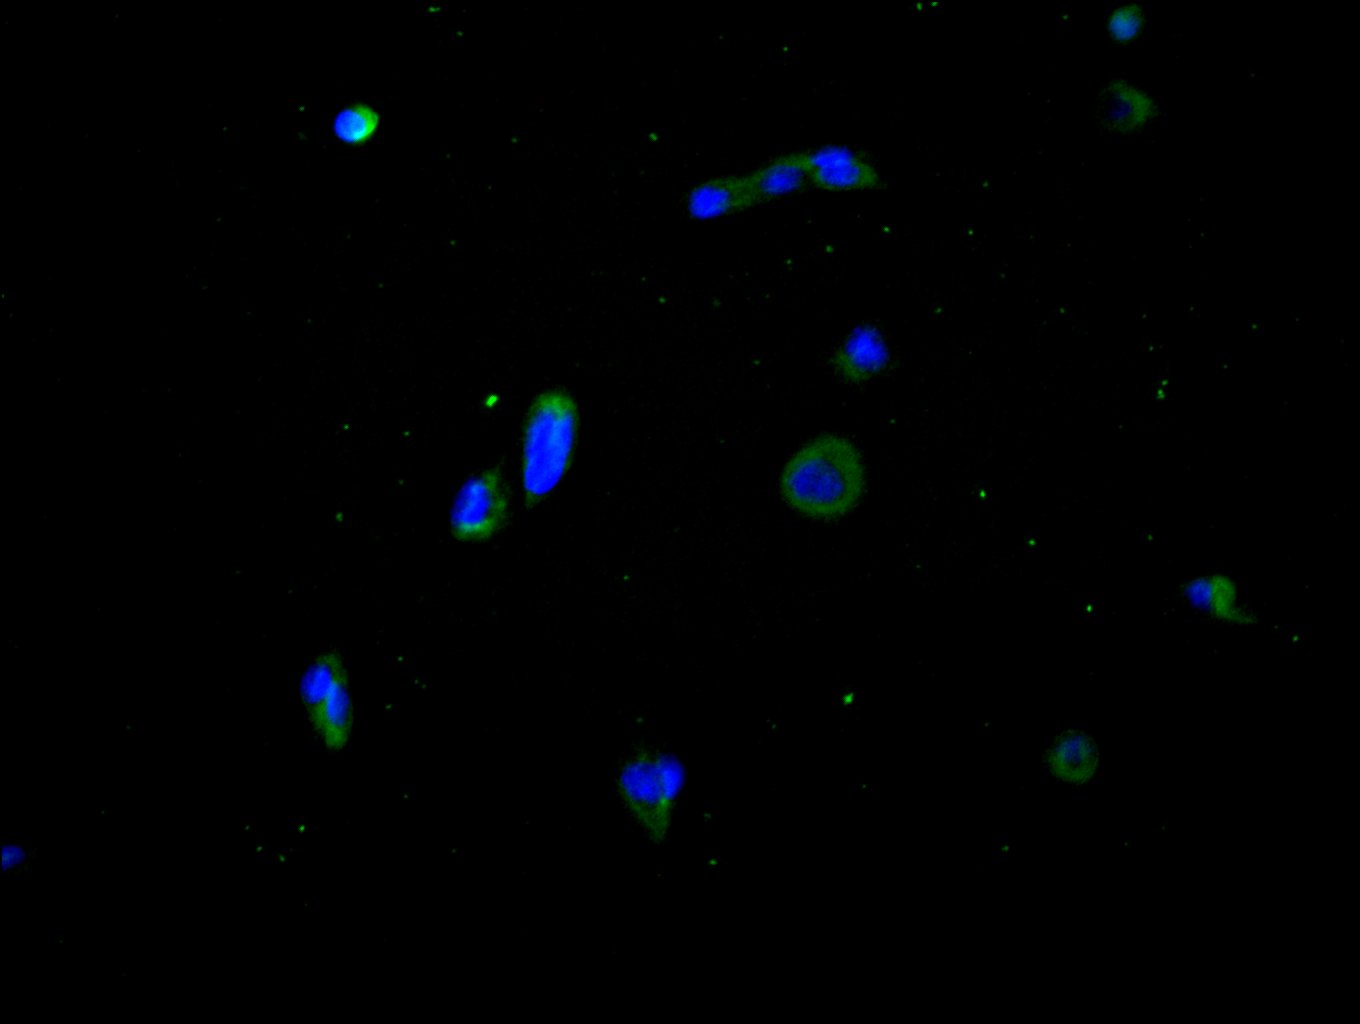

• Immunofluorescence staining of Hela cell with CSB-RA575353A0HU at 1:30, counter-stained with DAPI. The cells were fixed in 4% formaldehyde and blocked in 10% normal Goat Serum. The cells were then incubated with the antibody overnight at 4C. The secondary antibody was Alexa Fluor 488-congugated AffiniPure Goat Anti-Rabbit IgG(H+L).

• Immunofluorescence staining of Hela cell with 5% goat serum, counter-stained with DAPI. The cells were fixed in 4% formaldehyde and blocked in 10% normal Goat Serum. The cells were then incubated with the antibody overnight at 4C. The secondary antibody was Alexa Fluor 488-congugated AffiniPure Goat Anti-Rabbit IgG(H+L).